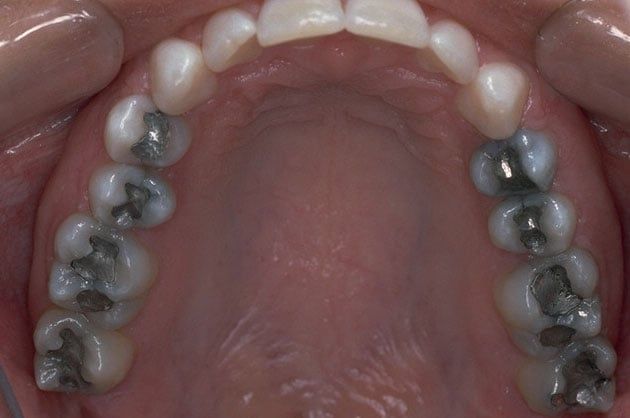

Replacing Old Fillings

There is now new technology that allows you to replace old silver and gold fillings with a more natural looking, composite filling. Composite fillings are bonded to the tooth and research has proven them to be about 90% as strong and healthy as natural tooth material.

Old fillings have been known to break down overtime, creating the potential for cavities, pain or even cracking the tooth itself! Composite fillings can be completed in a single visit, look and function like your natural teeth and have less of a chance of problems in the future.